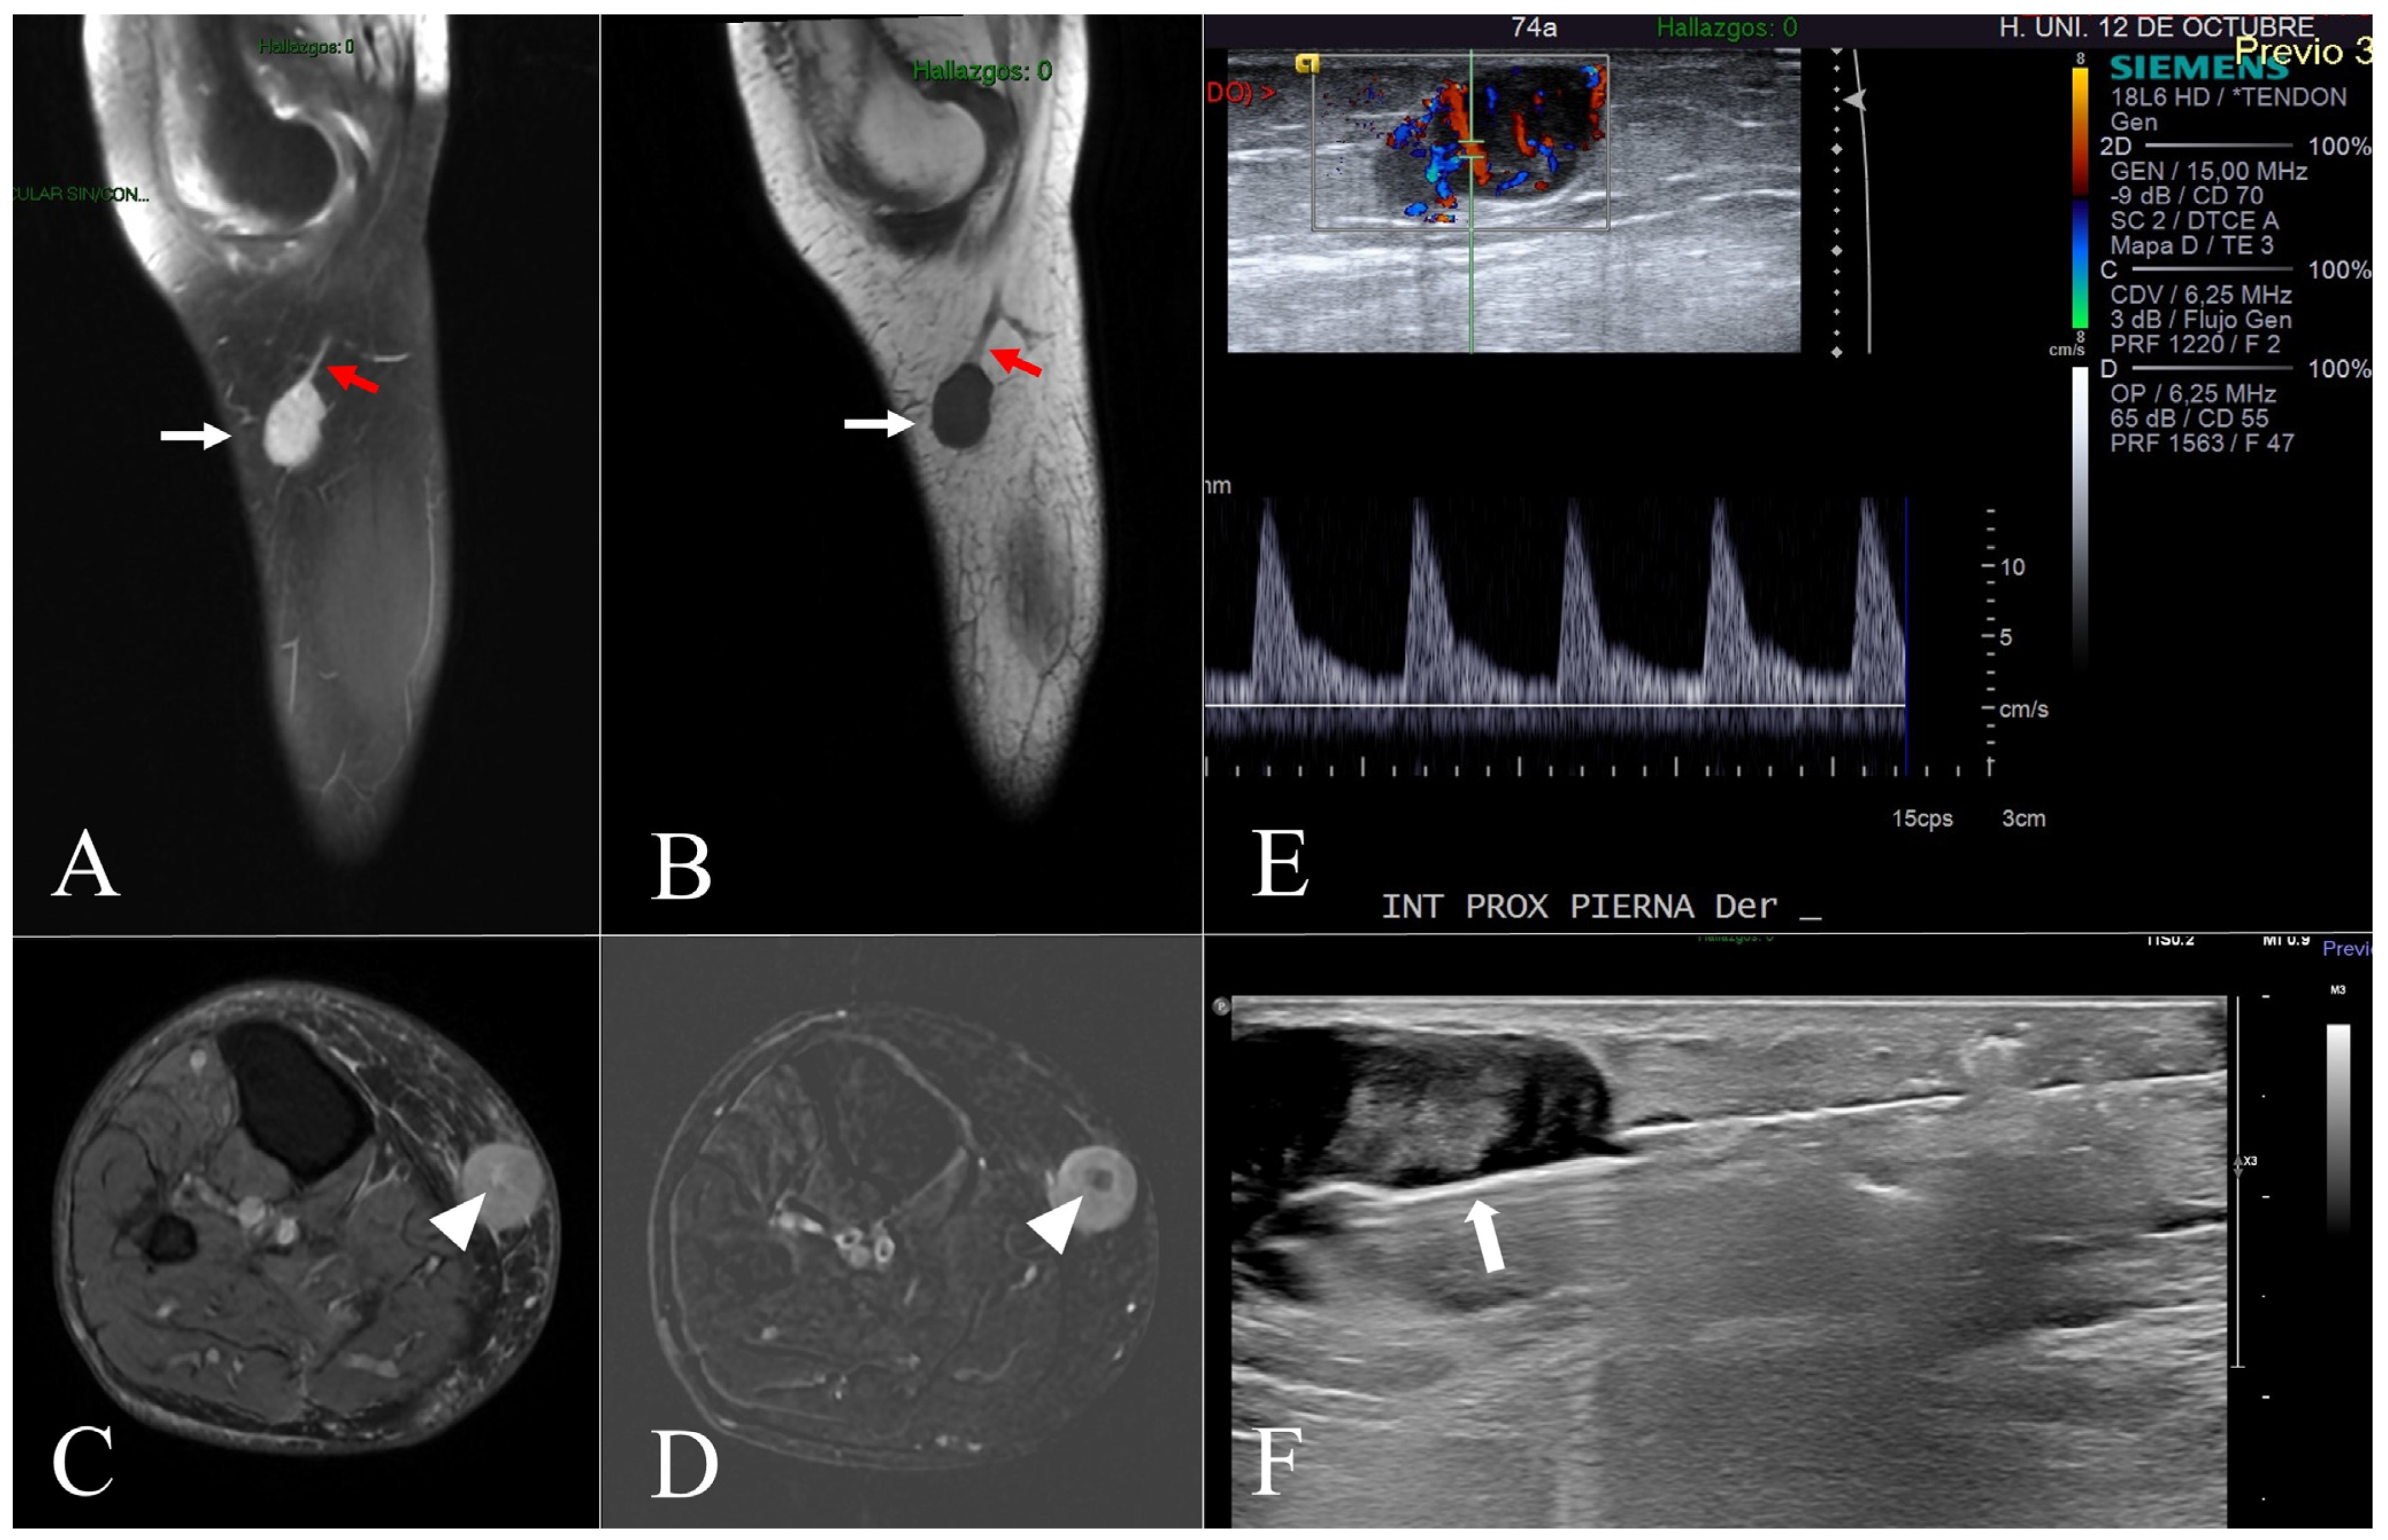

Figure 2.

Case 8. (A,B) = Sagittal DP fat-suppressed (A) and sagittal T1-weighted (B) MR images show a subcutaneous well-defined and homogeneous lesion (white arrows) in continuity with the saphenous vein (red arrows). (C,D) = Axial DP fat-suppressed (C) and digital subtraction post-processing images show homogeneous enhancement with central low attenuation representing necrosis (white arrowheads). (E) = A longitudinal ultrasound view of the right leg demonstrates a well-defined lesion located in the subcutaneous fat layer with patent internal vascularity. (F) = A longitudinal ultrasound shows the biopsy needle (white arrow), which has been advanced into the lesion under US guidance while avoiding crossing the fascia of the leg.